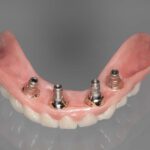

„Implantat-Chirurgie kompromittierter Patienten und was können wir für Gesunde daraus lernen?

OÄ Dr. Marie-Sophie Katz, Aachen

„Implantatprothetik – Unterschiede zwischen kompromittierten und gesunden Patienten“

Prof. Dr. Sven Reich